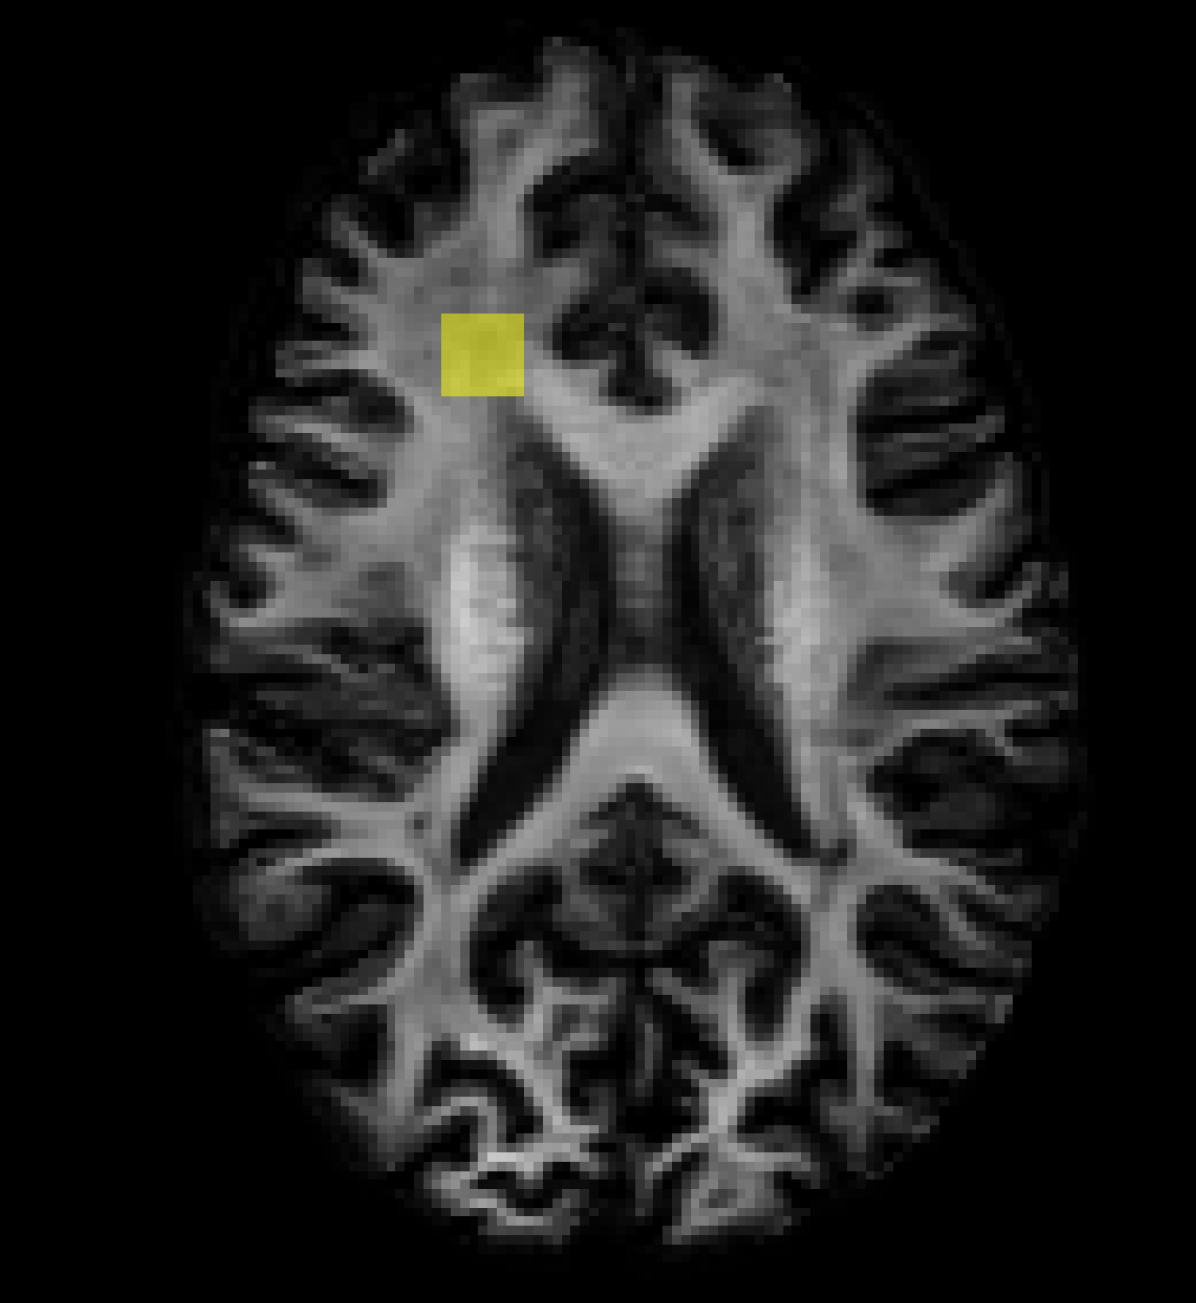

Table 3 summarises the performance in FBA in the low resolution baseline and model based reconstructions compared to the high resolution ground truth, whilst Figure 3 visualises a subset of reconstructed FODs within an axial slice. Here, all PCCNN models performed better than the low resolution baseline in all three sampling schemes in FOD ACC, and had lower AFD AE in the two lowest sampling schemes. The PCCNN models performed competitively against the RCNN. However, in the smallest sub-sampling scheme qin=6subscript𝑞in6q_{\mathrm{in}}=6, or equivalently 6.6%percent6.66.6\% of the original number of voxels, the RCNN performed slightly better. Whilst the low resolution data had lower AFD AE at qin=20subscript𝑞in20q_{\mathrm{in}}=20, the PCCNN models had, in the worse case, a relative increased mean error of approximately 6%percent66\%, compared to 35%percent3535\% increase in the RCNN model. Additionally, the PCCNN models had greater ACC compared to the low resolution baseline across all sub-sampling schemes, suggesting that their use in probabilistic tractography [33] and connectomics [4] would be beneficial.

Refer to caption

(a) ROI

(b) High Resolution

(c) Low Resolution

(d) RCNN

(e) PCCNN-Bv-Sp

Figure 3: Fibre orientation distributions (FOD)s in one ROI slice for a test subject with metrics derived from both input data and inferred data using various models. Models use single-shell data (b=1000s/mm2𝑏1000ssuperscriptmm2b=1000\mathrm{s/mm^{2}}) with angular dimension size qin=10subscript𝑞in10q_{\mathrm{in}}=10 as input, and produce b=1000s/mm2𝑏1000ssuperscriptmm2b=1000\mathrm{s/mm^{2}} inferred data with angular dimension size 808080. Low Resolution denotes FODs derived from single-shell input only.